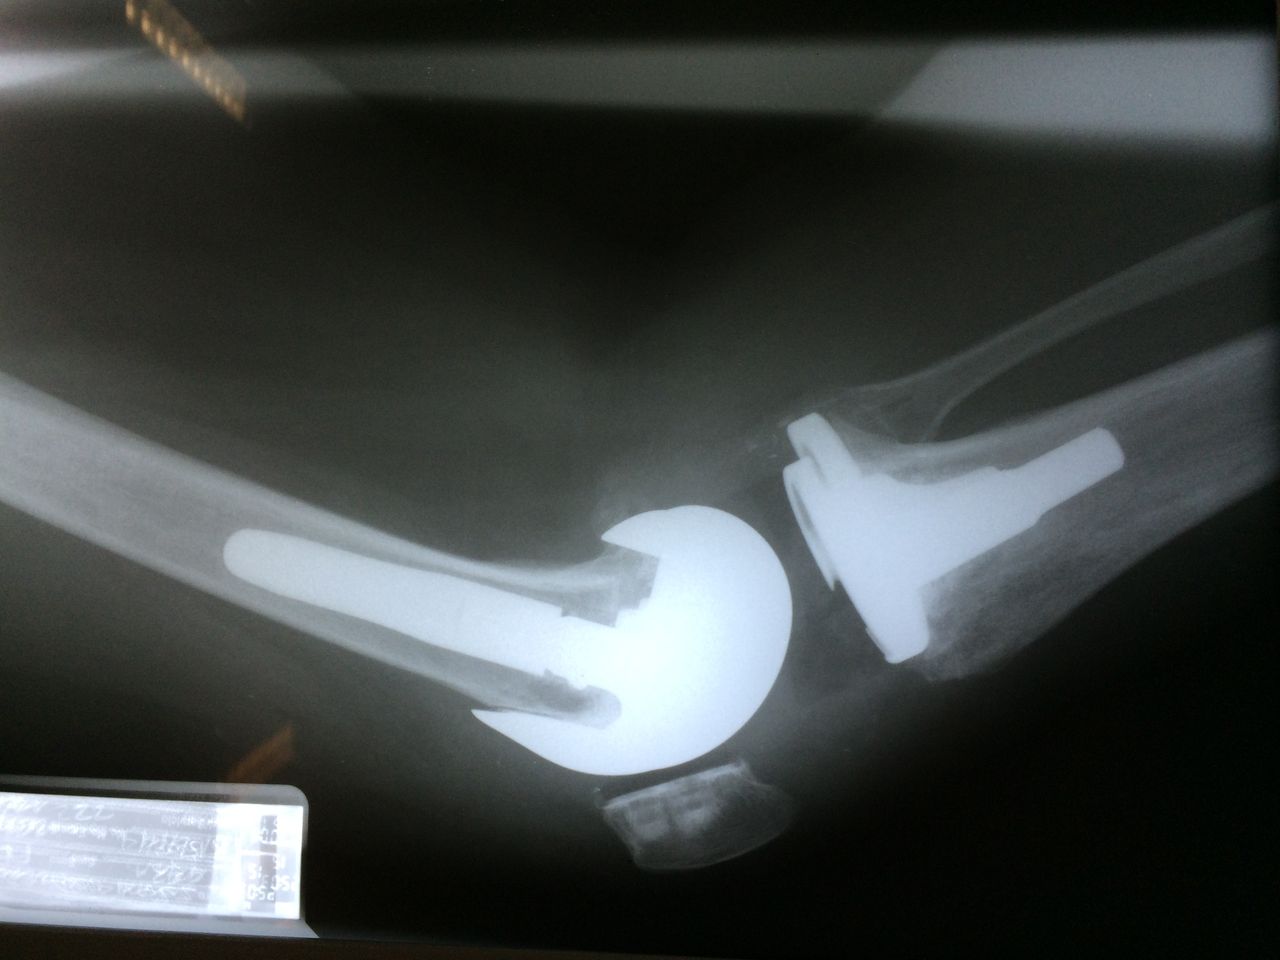

Artroplastia de la cadera con prótesis total

El desgaste articular de la cadera, se traduce en dolor para el paciente afectando su calidad de vida. Existe un procedimiento quirúrgico mediante el cual, se realiza una sustitución de la articulación de la cadera por un implante que realiza la función de la misma. De esta manera se quita el dolor por completo del paciente restituyendo la anatomía normal, y mejorando de manera significativa la calidad de vida del paciente.

Rescate prótesis, variantes postprótesis

Cuando una prótesis total de cadera, rodilla o de hombro ha fracasado, o ha llegado a su tiempo estimado de vida útil, se afloja, en algunas ocasiones, este proceso implica pérdida de hueso. Afortunadamente, existen procedimientos quirúrgicos, con implantes especiales para restaurar la función de la articulación previamente sustituida por una prótesis articular. Siempre es posible realizar un nuevo procedimiento quirúrgico con la finalidad de rescatar una prótesis articular.